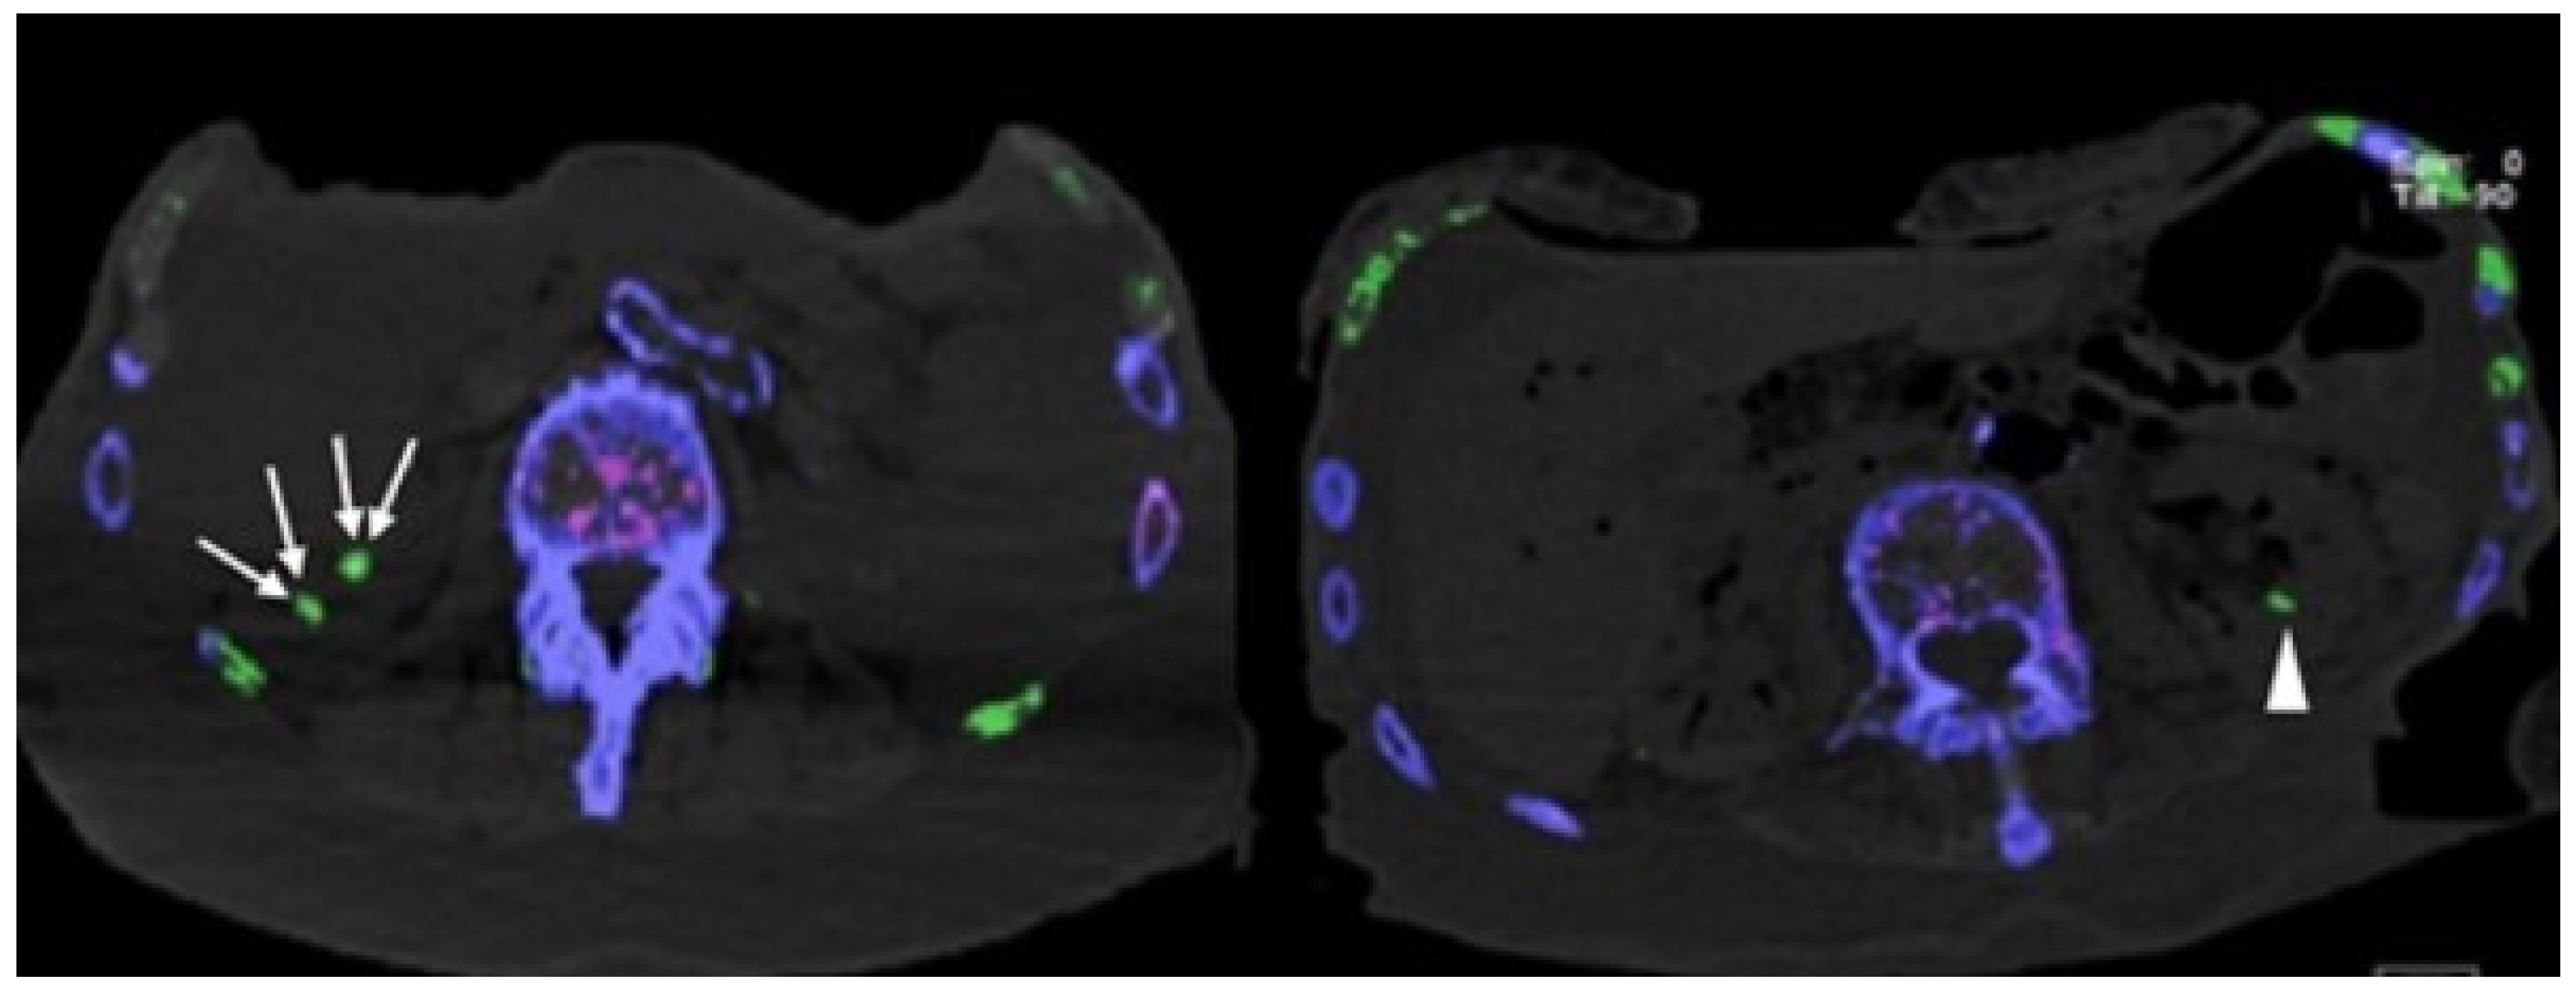

- Klauser, A.S.; Halpern, E.J.; Strobl, S.; Gruber, J.; Feuchtner, G.; Bellmann-Weiler, R.; Weiss, G.; Stofferin, H.; Jaschke, W. Dual-Energy Computed Tomography Detection of Cardiovascular Monosodium Urate Deposits in Patients With Gout. JAMA Cardiol. 2019, 4, 1019–1028. [Google Scholar] [CrossRef]